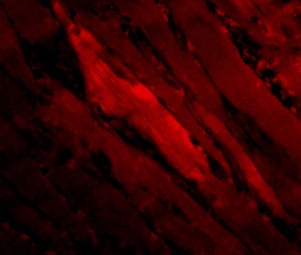

Immunofluorescence of SHP2 in Human Skeletal Muscle cells with SHP2 antibody at 20 ug/ml.